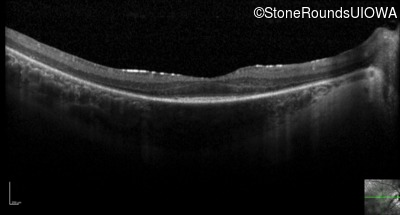

Optical Coherence Tomography - Right - 20/100 -1

Exemplar / OCT Stack